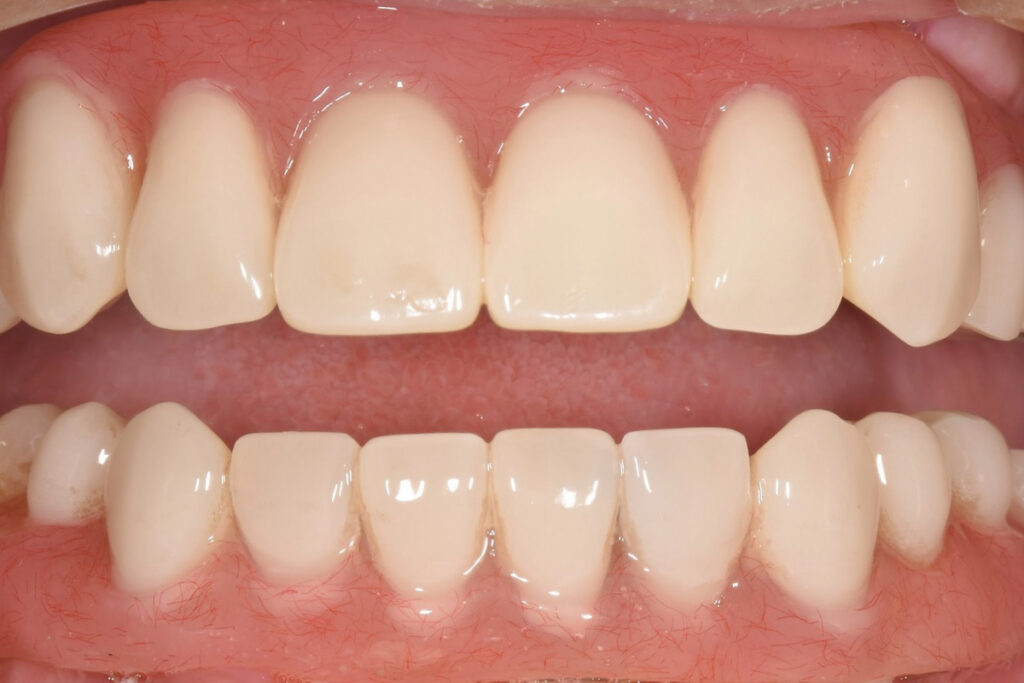

■結果としての状態

噛む機能の回復とともに、長期管理を前提とした設計が成立しました。「設計が成立」とは、手術が終わったという意味ではありません。10年単位で維持できる見通しが構造として成立したということです。

治療は計画どおり進行し、無理のない形で咬合を回復しました。患者が得るのは「噛める」以上に、これなら続けられるという見通しです。高齢層にとって、ここが最も大切です。